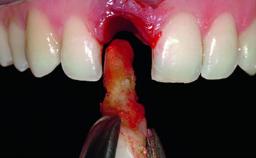

Replacement of a Failing Restored Upper Right Central Incisor, Ridge Preservation and Early Placement of an RC Bone Level Implant

A 23-year-old female, healthy and non-smoking patient had had tooth 11 temporarily restored following a trauma in adolescence. As the patient’s growth had since come to an end and the crown had fractured, she requested an implant-supported restoration of tooth 11. Moreover, the contralateral tooth 21 presented an old composite restoration at the mesial incisal edge. The periodontal tissues were healthy with periodontal probing depth values below 3 mm, but some inflammation was observed around the semi-submerged root of tooth 11.